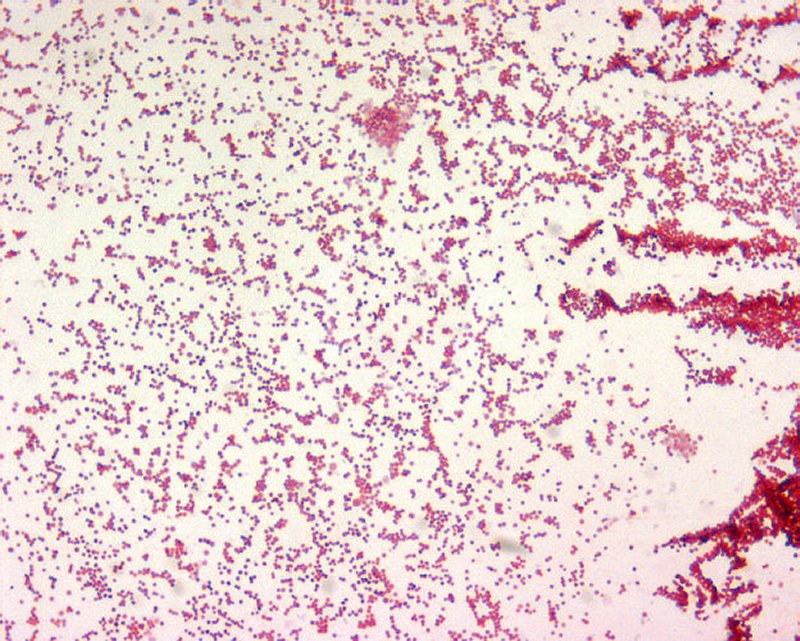

Tularemia Fever

Tularemia Pictures